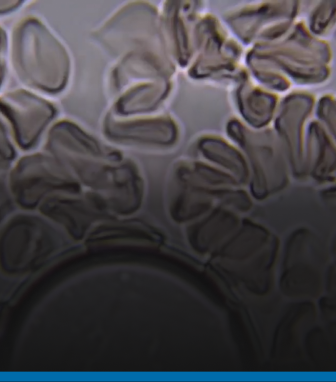

CARDIOVASCULAR DISEASE

Learn about how we’re housing the Victorian Heart Hospital on our Clayton campus. It’s Australia’s first dedicated cardiac hospital where education, research, clinical practice and patient care will come together in a state-of-the-art, strategically located facility.